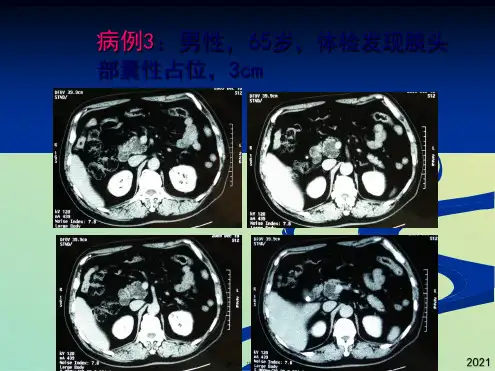

粘液性囊腺瘤

临床表现

✓ 大多数是女性,年龄比SCNs年轻10岁,平均年龄48–52岁。 MCNs相关的浸润性癌平均在64岁,需要更长的时间进展为

明显的恶性。

✓ 25–50%的病人没有症状。腹痛是常见症状。4–17%的病人

可能出现急性胰腺炎,比IPMN少。

✓ 大部分MCNs位于胰体或胰尾,大小平均5–6 cm,比SCNs 和IPMNs大1cm,MCNs相关的浸润性癌直径更大,平均7cm。